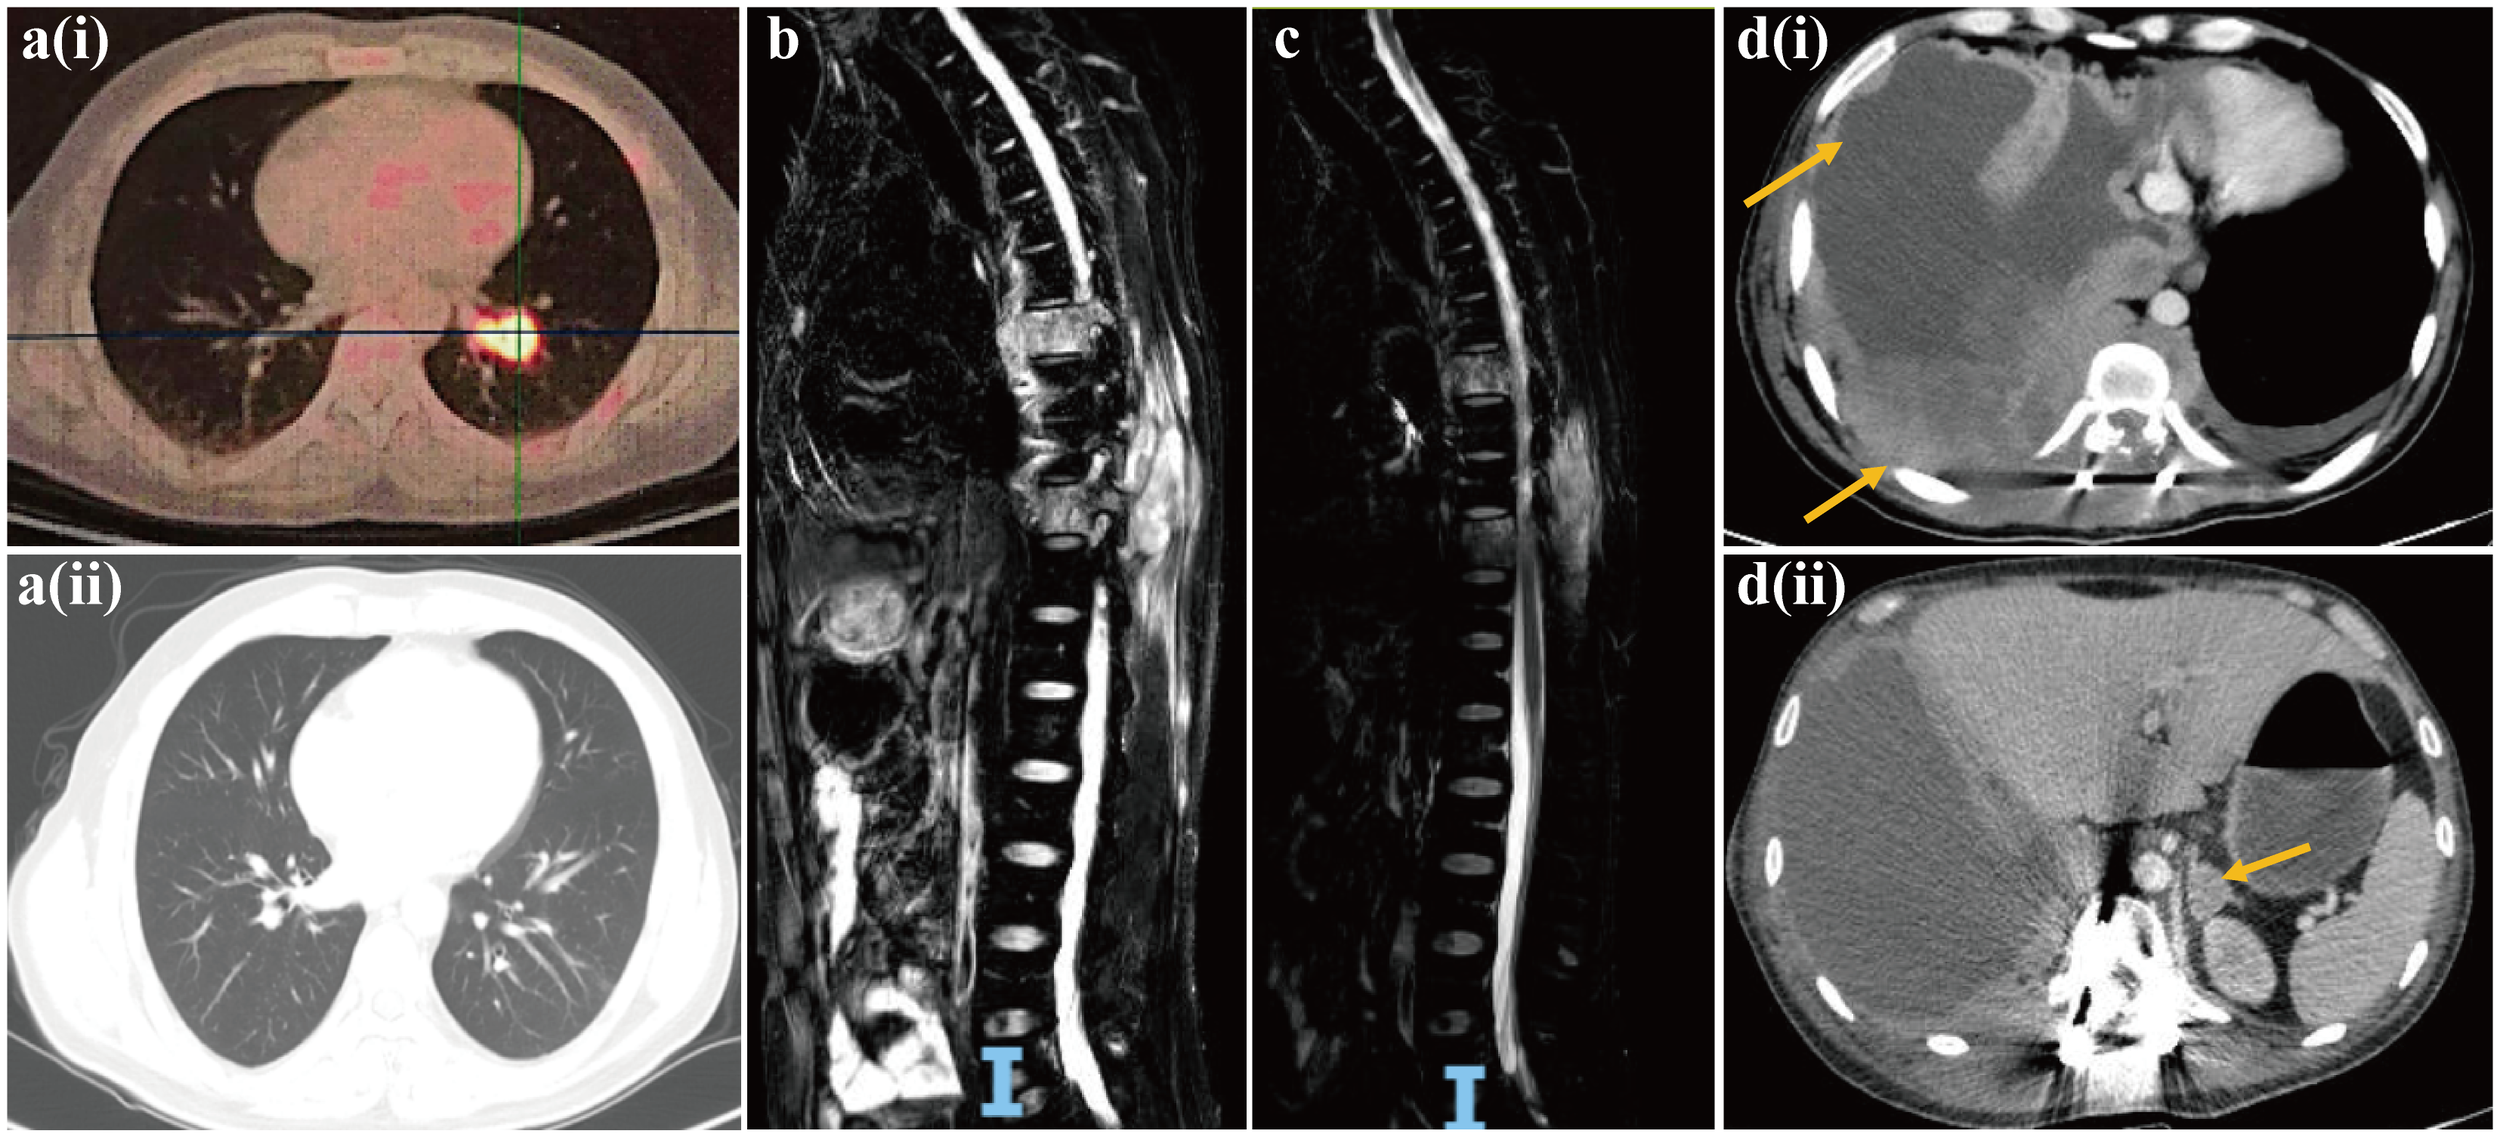

The patient exhibited a favorable functional status (score of 0) according to the Eastern Cooperative Oncology Group Performance Status (ECOG PS) scale, and started receiving chemotherapy (etoposide plus carboplatin) combined with the anti-PD-1 inhibitor sintilimab from December 2022. After two treatment cycles, a chest and abdominal CT scan on February 14, 2023, revealed reduced mediastinal lymph nodes and stable status of bone metastases in the pubis, scapula, ilium, ribs and lumbar vertebra. The lesion diagnosed in the lower lobe of the left lung at baseline diagnosis had resolved after two treatment cycles, and the efficacy was evaluated as a partial response (Figure 3a). Despite stable bone metastases, the patient experienced gradual aggravation of bone pain and discontinued his chemotherapy. In February 2023, the patient’s ECOG PS was still 0, and he was enrolled in a phase I clinical study for patients with advanced solid tumors or lymphoma (ChiCTR2000040198). Subsequently, he received the bromodomain and extra-terminal motif inhibitor (BET-i) “NHWD-870 HCl” for targeted therapy. This treatment significantly alleviated his severe bone pain, and a CT scan in April 2023 revealed stable disease in both thoracic and bone metastases. Four months later, examination by magnetic resonance imaging (MRI) showed multiple bone and soft tissue metastatic lesions, with worsening of bone destruction and increased bone pain. The disease progressed in June 2023 after 4 months of treatment with BET-i (Figure 3b).

Figure 3

Computed tomography images of pulmonary NUT carcinoma pre-[a(i)] and post [a(ii)] two treatment cycles of chemotherapy (etoposide plus carboplatin) in combination of PD-1 inhibitor sintilimab. Magnetic resonance image of progressive disease with multiple bone and soft tissue metastatic lesions, and worsening of bone destruction after 4 months of treatment with BET inhibitor (b). Magnetic resonance image of reduction in multiple soft tissue lesions, and the improvement of spinal stenosis at the seventh and tenth thoracic vertebrae following chemotherapy in combination of anti-angiogenesis agent bevacizumab and radiotherapy (c). Computed tomography images of multiple lesions developing in the pleura, chest wall [d(i)] and adrenal gland [d(ii)].

In July 2023, the patient’s ECOG PS remained at 0, and he underwent another round of chemotherapy (albumin-bound paclitaxel plus carboplatin) in combination with the anti-angiogenesis agent bevacizumab. Concurrently, he received radiotherapy for vertebral tumors at the dose of 40Gy/4Gy/10f. An MRI examination in August 2023 revealed a reduction in multiple soft tissue lesions, and the spinal stenosis at the seventh and tenth thoracic vertebrae showed improvement (Figure 3c). However, in September 2023, the bone and soft tissue metastatic lesions progressed again, along with worsening of spinal stenosis. Given the partial response after only two cycles of first-line chemotherapy with sintilimab, and based on his favorable ECOG PS score of 0 and discontinuation of the regimen due to the gradual aggravation of bone pain rather than due to disease progression, the medical team recommended rechallenge with first-line chemotherapy (etoposide plus carboplatin) combined with sintilimab. Unfortunately, after only one treatment cycle, the patient developed neurothlipsis, leading to paraplegia due to the refractory spinal metastasis. Subsequently, in November 2023, decompression and excision of spinal canal lesions were performed. The postoperative pathology confirmed metastatic NC, with positively stained NUT in IHC analysis.

In December 2023, the patient’s functional status deteriorated (ECOG PS score: 2). He received single-agent chemotherapy with doxorubicin, combined with the histone deacetylase inhibitor (HDAC-i) tucidinostat for epigenetic therapy. Unfortunately, his health condition rapidly worsened, with multiple lesions developing in the pleura, chest wall and adrenal gland (Figure 3d). Finally, in January 2024, the patient succumbed to acute respiratory failure and dyscrasia, with an OS period of 15 months. The timeline of this patient’s treatment was depicted in Figure 4.